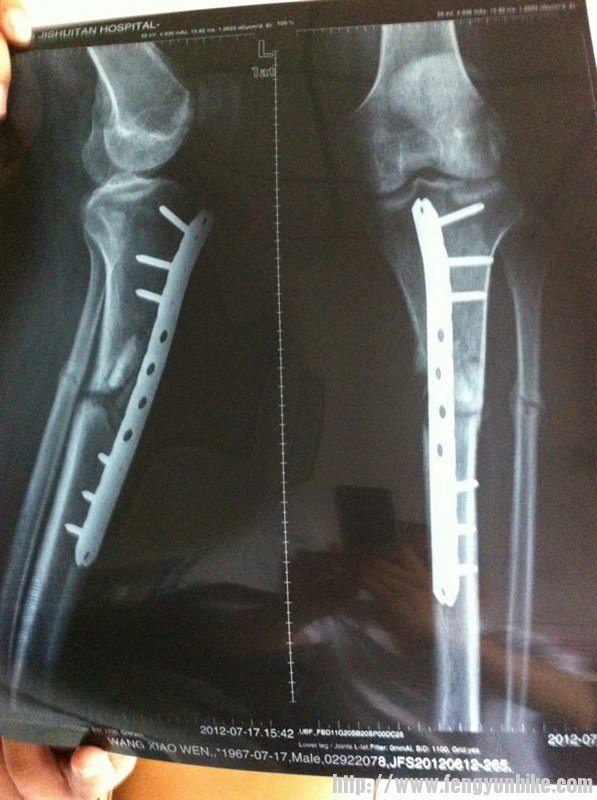

我是3月11日骑车造成骨折,当天送往积水潭医院,3月15日做完手术,至今4个半月了,还没长好。问问有懂的吗?帮我看看片子,会不会是骨不连?我该咋办?片子在我qq空间里。QQ号64355985.

这是4个月的片子

看片子应该是粉碎性骨折

胫腓骨双骨折 骨折线清晰可见 骨痂形成不是很明显啊

钢板内固定 对位对线良好